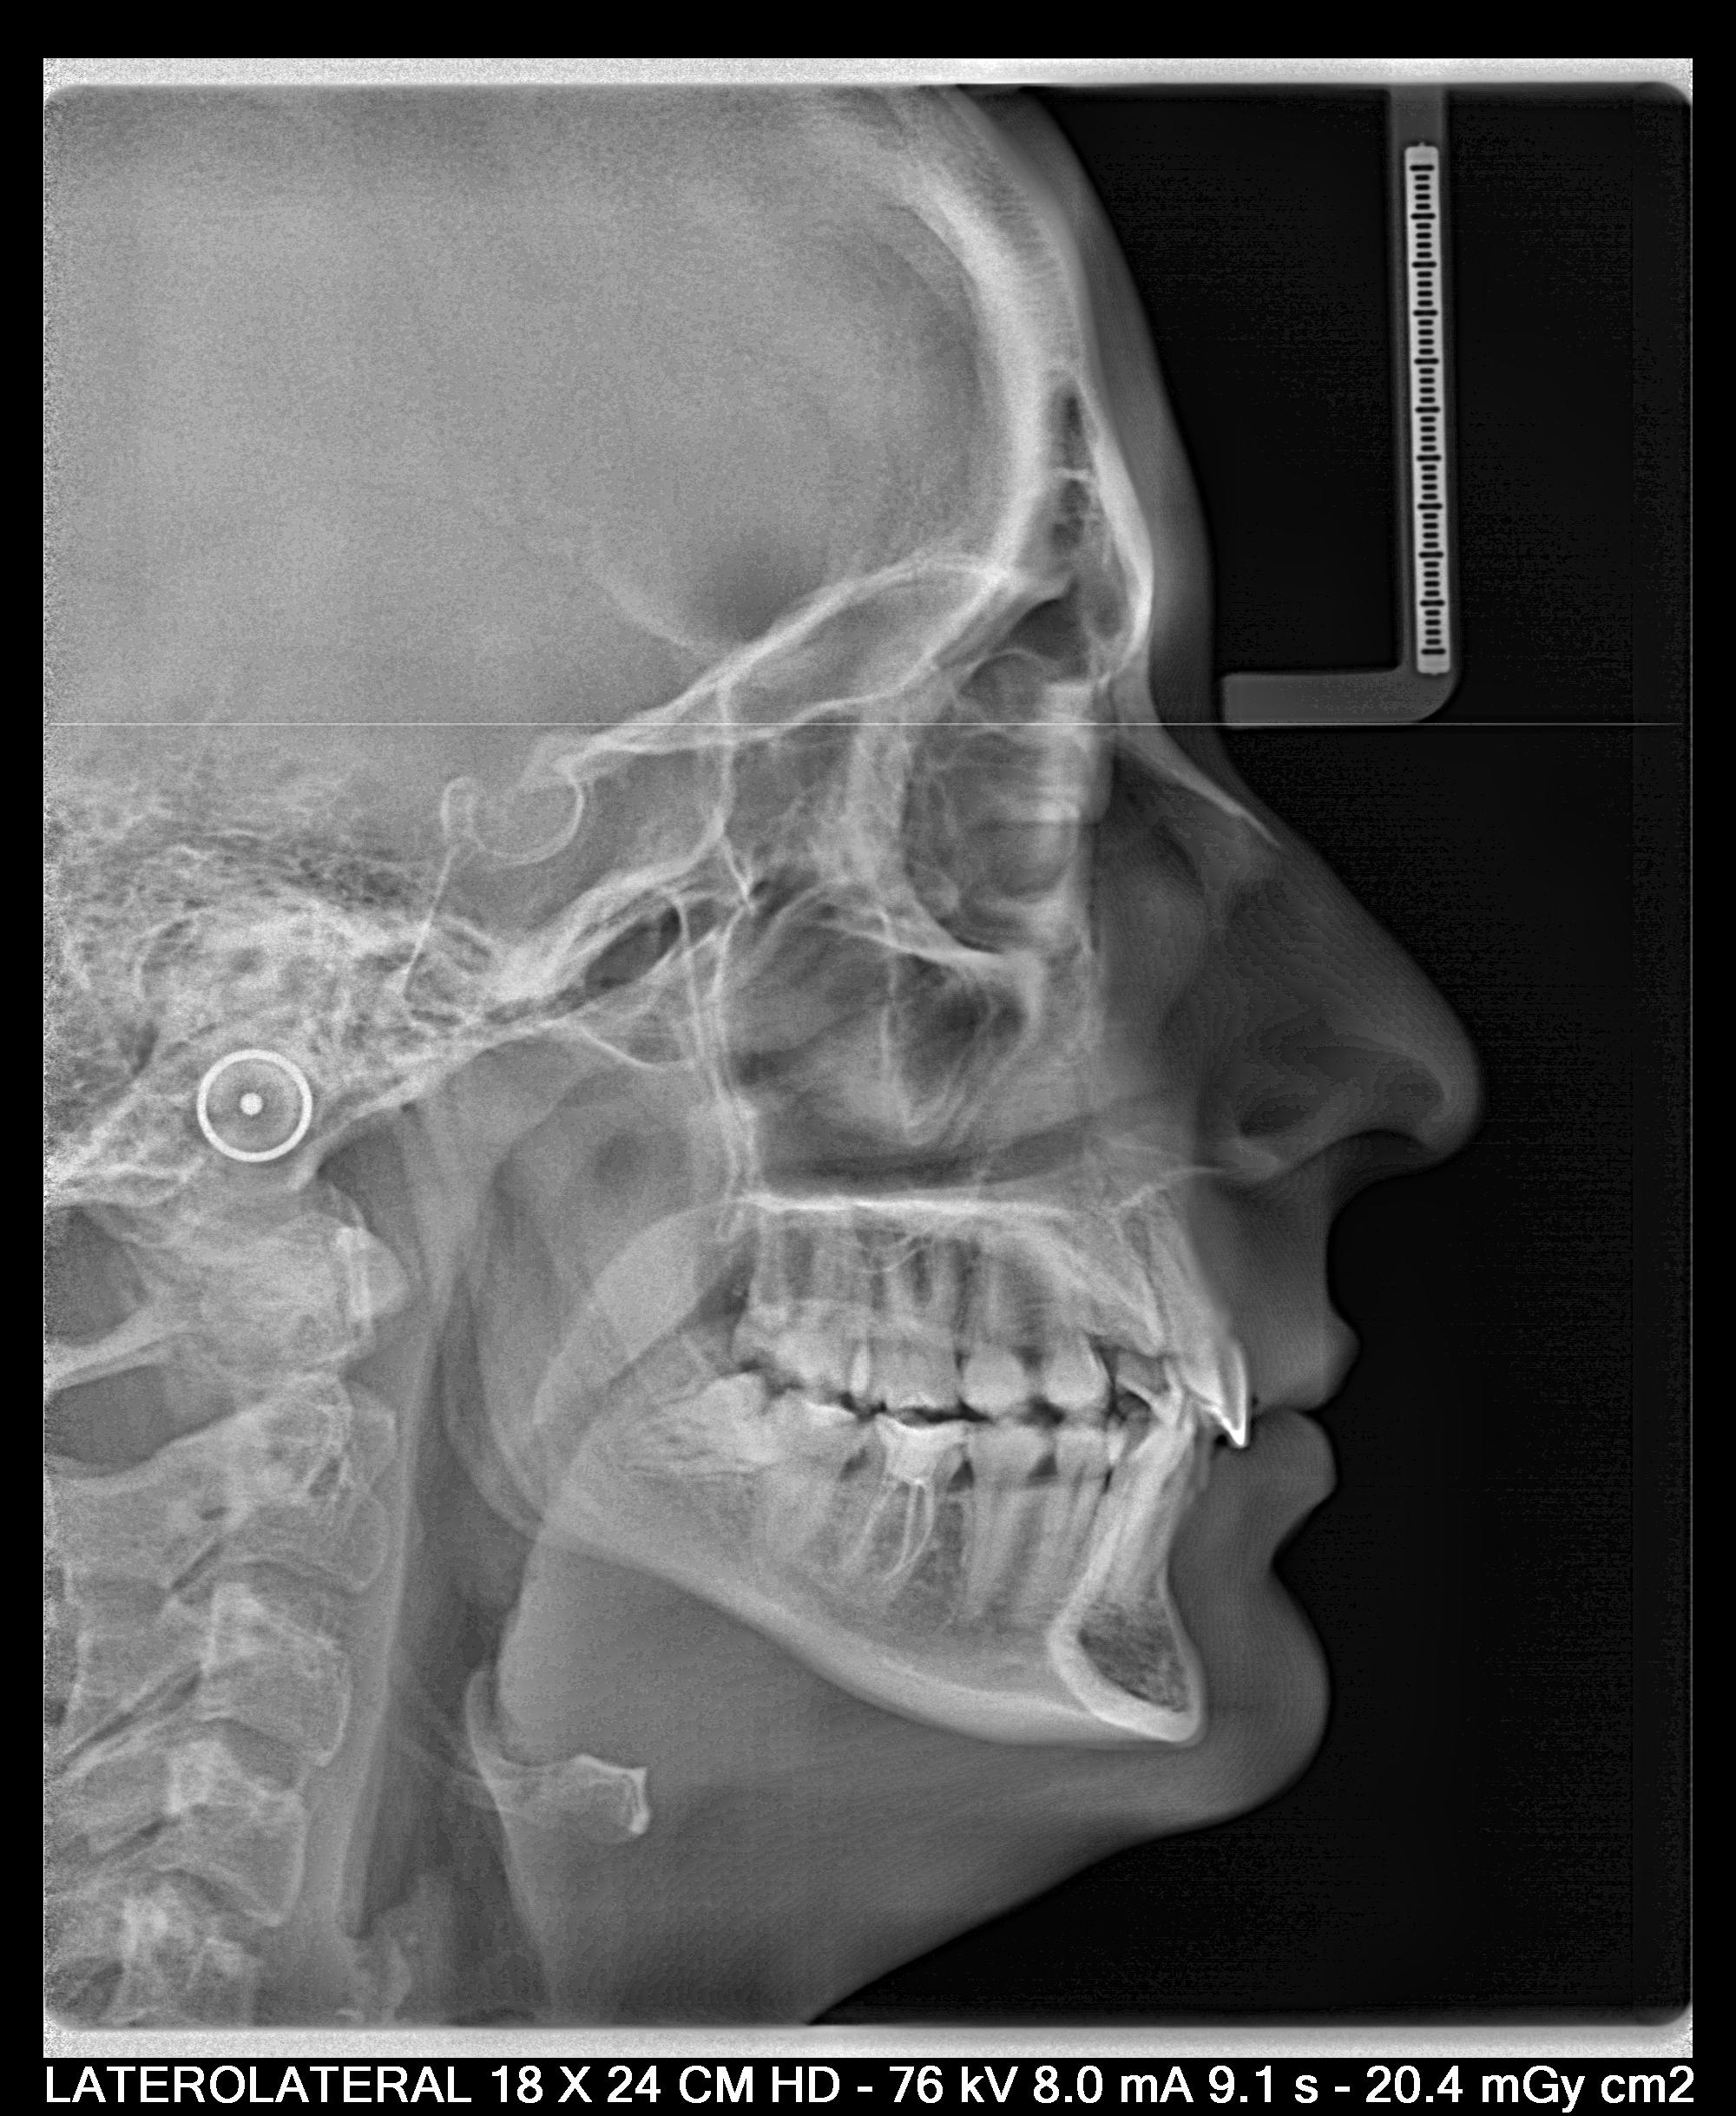

B) ¿Cómo se diagnóstica? Palpación a los 9-10 años; ortopantomografía; CBCT.

-Particularmente, cuando reconozco mediante la palpación o la ortopantomografía que hay una canino incluido por palatino, por protocolo, como en este caso, hago un CBCT. El motivo es porque esta prueba diagnóstico nos permite reconocer de una manera tridimensional el lugar del canino en la boca.

E) ¿Cómo de complicado es mi canino  incluido? ( Método Erickson y Kurol) (fotografías de interés)

-Altura del canino respecto al plano oclusal. A mayor distancia, mayor dificultad.

-Angulación entre la línea del canino y una perpendicular horizontal desde la zona apical. A menor angulación, mayor dificultad. (31 grados: mal pronóstico)

Posición del ápice ( punto clave, pues el movimiento radicular es extremadamente complicado). A mayor distancia del ápice del canino respecto a su posición ideal mas dificil.

Relación con la línea media. A menor distancia de la línea media, mayor dificultad.

Atendiendo a estos criterios, en nuestro caso, el pronóstico es bueno. Ya que tres de los cuatro criterios son favorables: el ápice se encuentra en una posición ideal, la distancia al plano oclusal no es mayúscula y la inclinación es mayor a 31 grados. Solo la posición de la corona cerca de la línea media aumentaría la dificultad.